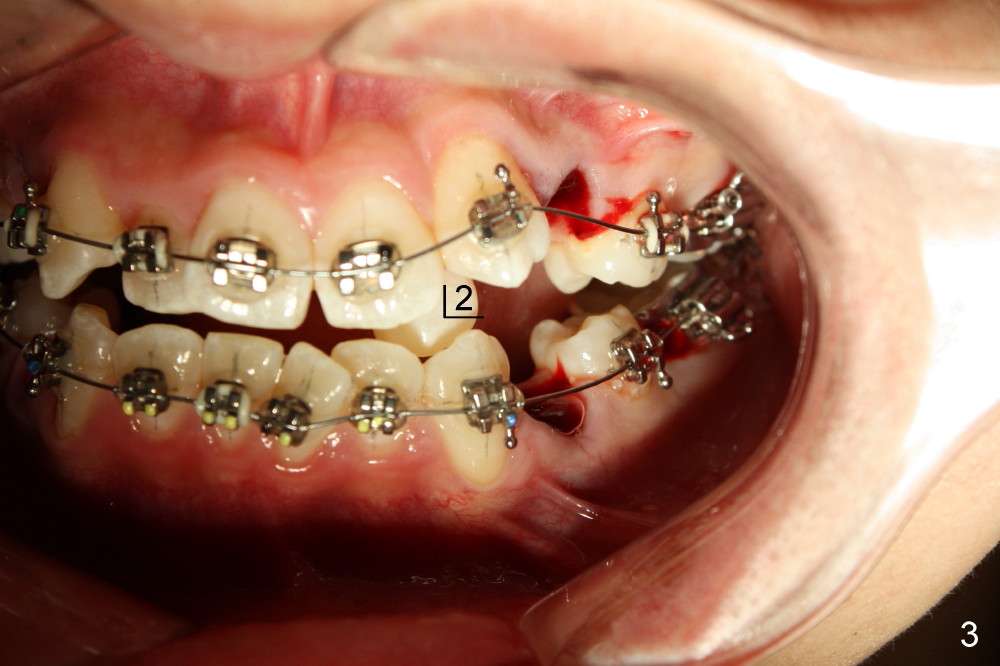

David, 16 years old, has severe crowding, midline deviation (Fig.1: dashed lines), and UL2 complete blockout (Fig.3: 2). Orthodontic treatment starts with extraction of four of the 1st bicuspids (Fig.2,3: .014 Niti).